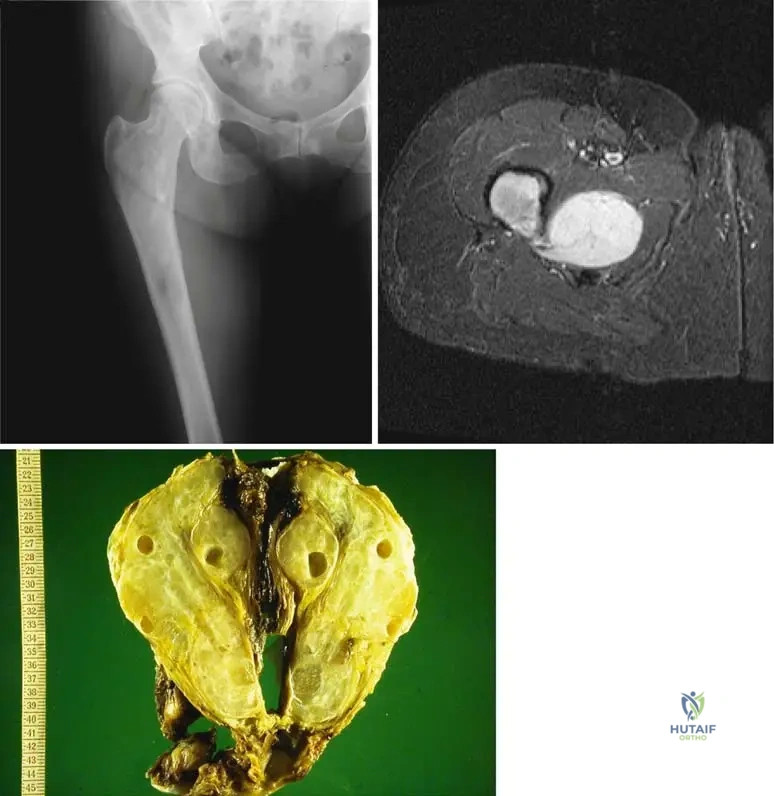

A 58-year-old female presents with a new, firm, non-tender mass in her right upper arm, accompanied by diffuse arm pain. She is cachectic and has a known history of lung cancer. Radiographs reveal extensive bone destruction in the humerus with a large associated soft tissue component. Which of the following primary tumors is most frequently associated with bony metastases?

Correct Answer: D

Rationale: The clinical text lists "Lung, breast, prostate, kidney, and thyroid cancers are the most frequent primary tumors associated with bony metastases." Lung cancer is explicitly mentioned and is consistent with the vignette and the provided image (Fig. 8.116) which shows a cachectic patient with lung cancer and a large soft tissue extension. Lymphoma (C) can involve bone but is not listed among the most frequent primary tumors causing bony metastases in the text.